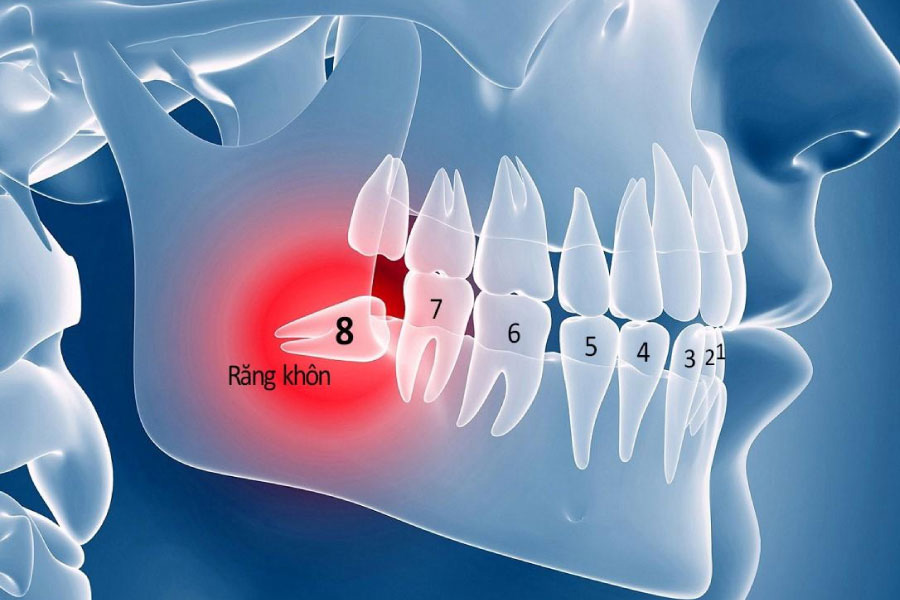

Răng khôn (hay còn gọi là răng số 8) thường mọc trong độ tuổi 17 – 25. Mỗi người trưởng thành sẽ có 32 chiếc răng gồm 4 răng khôn, 2 cái hàm trên và 2 cái hàm dưới. Tuy nhiên, không phải ai cũng mọc đầy đủ cả 4, có người chỉ 1 – 2, thậm chí có người không mọc.

Răng khôn là răng mọc cuối cùng trên cung hàm

Do răng khôn mọc sau cùng nên gần như không còn đủ khoảng trống để mọc lên và thường xảy ra tình trạng răng mọc sai: Mọc ngầm, mọc lệch, mọc ngược,… gây đau nhức, khó chịu. Vì vậy, hầu hết mọi người đều thực hiện tiểu phẫu nhổ răng khôn để tránh các biến chứng.